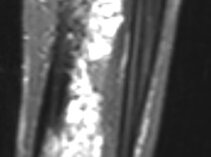

- MRT, ggf. mit TWIST-Angiographie (zur exakten Darstellung der Gefäßfehlbildung, deren Ausdehnung und Durchblutung, diese Informationen werden zur Abwägung von Therapieoptionen benötigt)